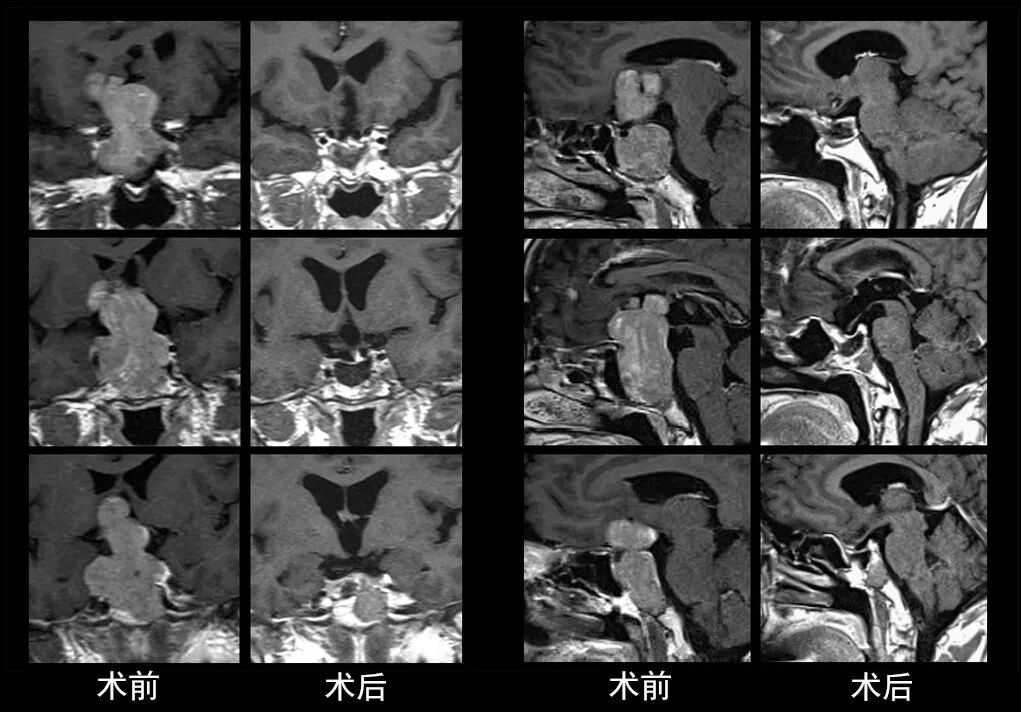

本研究中采用联合手术策略的代表性病例展示:

左右滑动查看更多

图片

case 1

case 2